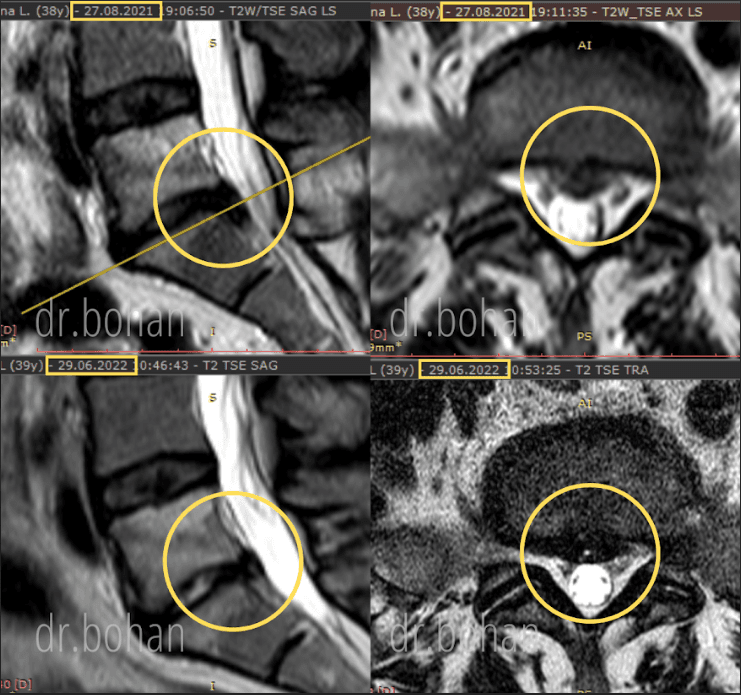

Метод лікування грижі шляхом стимуляції резорбції в Україні був впроваджений у 2020-2021 роках.  Алгоритм оцінки грижі на предмет резорбції, що використовується у клініках – є авторським, розроблений лікарем Боханом А.Ю.